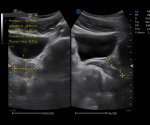

Urology

· In-plane Biopsy Guidance indicates the insertion path and needle tip position during biopsy operation.

· Out-of-plane Biopsy Guidance supports preset of needle size and insertion depth to minimize the risk of potential damage to surrounding tissues.

· Compatible with Bi-plane probe for efficient urology examination.

Bi-plane Dual Micro-convex Probe

Bi-plane Linear and Micro-convex Probe